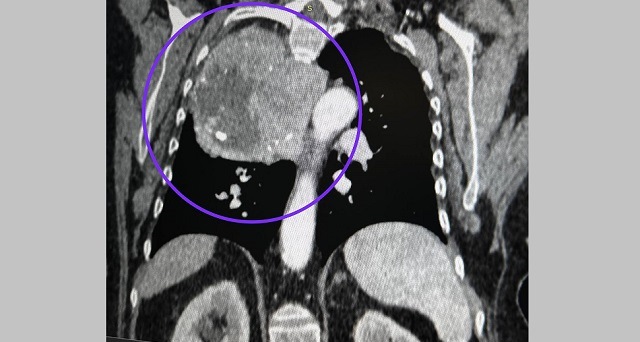

В Казани торакальные хирурги РКБ спасли 75-летнюю пациентку, которую едва не задушила сначала одна опухоль, а затем другая. Историю рассказала пресс-служба медучреждения.

Но в этот раз опухоль выросла из нижнего полюса щитовидной железы и заняла треть грудной клетки. По признанию медиков РКБ, в их практике такое образование встречается впервые.